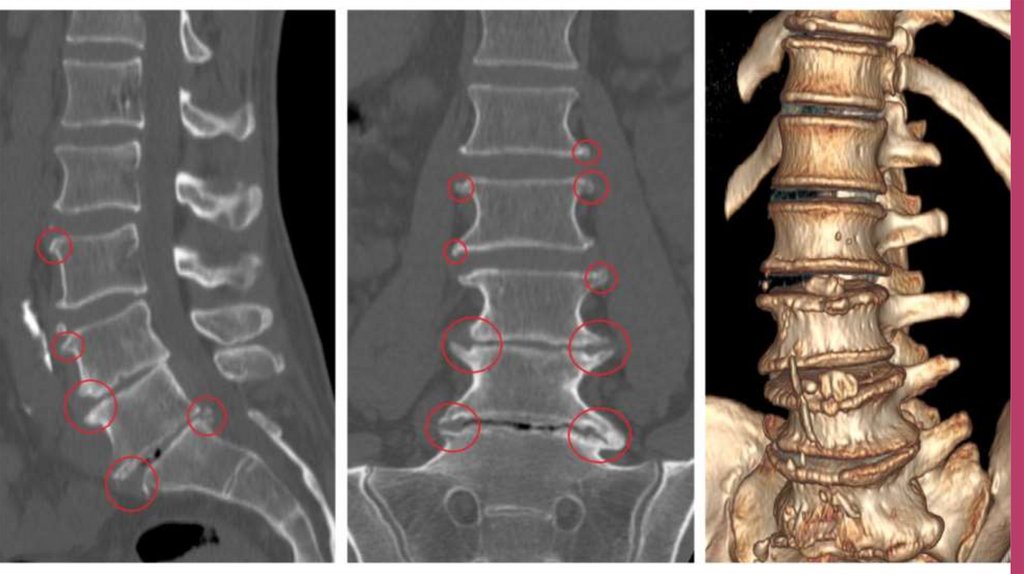

Для точно определения первопричин и места локализации

дегенеративных процессов проводят рентгенографию, компьютерную

томографию, МРТ. При исследовании очагов воспаления рядом с

дугоотросчатыми суставами используют радиоизотопное сканирование

спины.

А для обнаружения синдрома позвоночной артерии применяют МСКТангиографию. В редких ситуациях вводят диагностические блокады.

Если у пациента произошло уменьшение или полное исчезновение

болевого синдрома, то у него точно есть спондилоартроз.